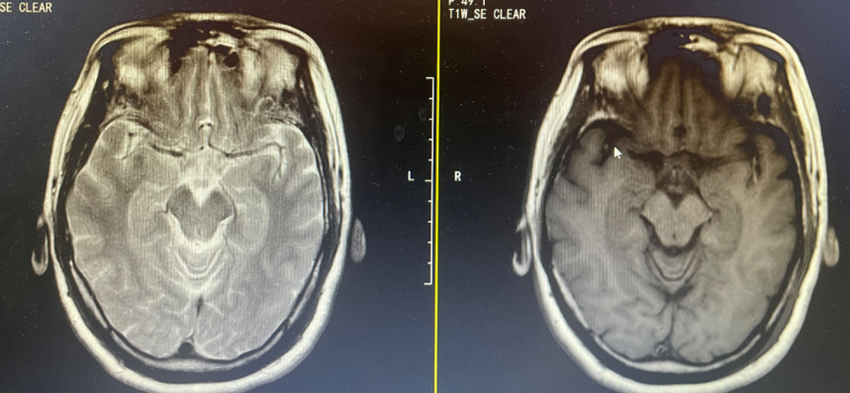

患者头颅检查片